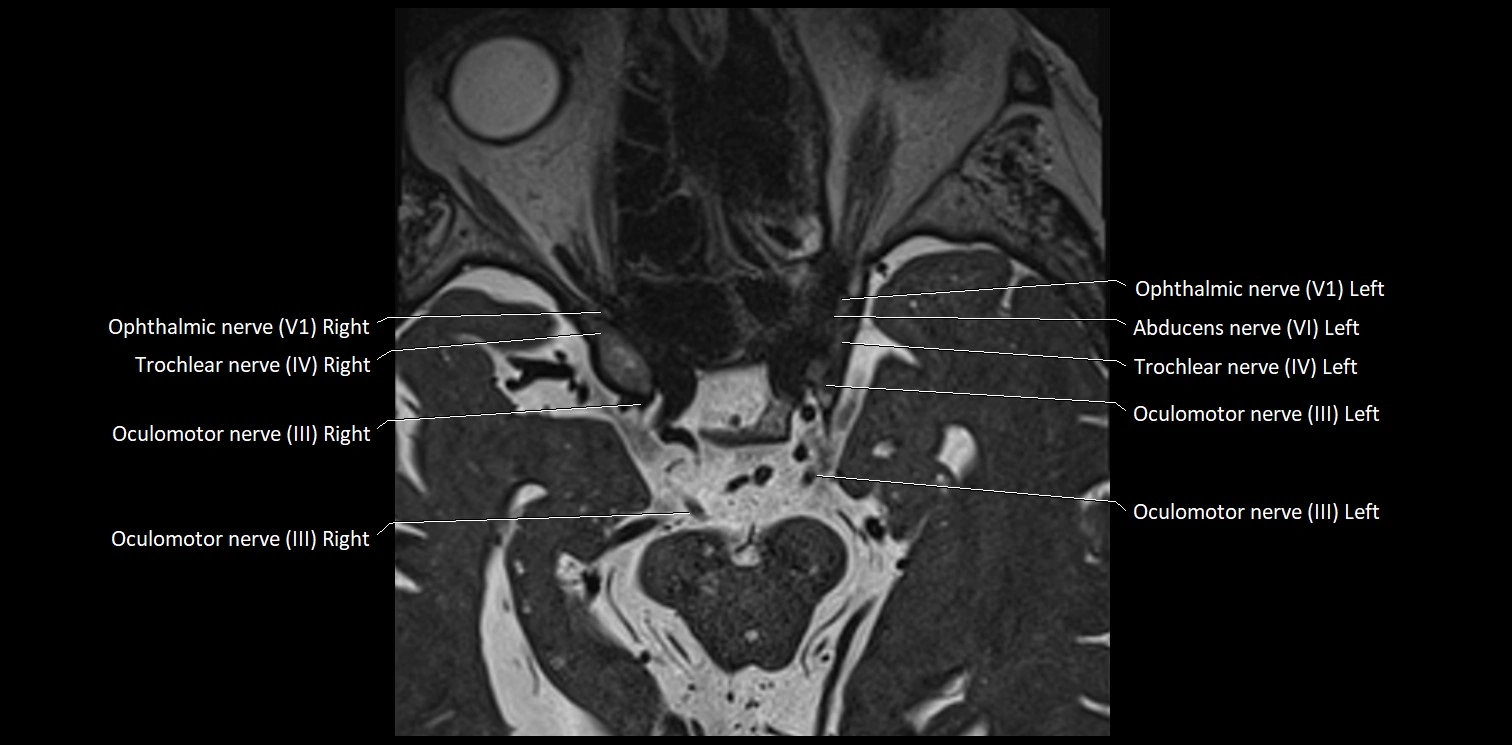

MRI Appearance

• The abducens nerve is a small, thin, linear structure

• Best visualized on high-resolution T2-weighted 3D MRI sequences (e.g., FIESTA or CISS)

• Seen as a hypointense (dark) line running from the brainstem at the pontomedullary junction, traversing the prepontine cistern, and entering Dorello’s canal under the petrosphenoidal ligament, then into the cavernous sinus, and finally the orbit

• May be challenging to visualize in standard MRI due to its small size

• Pathology may be inferred by absence, displacement, or enhancement of the nerve

MRI images

image